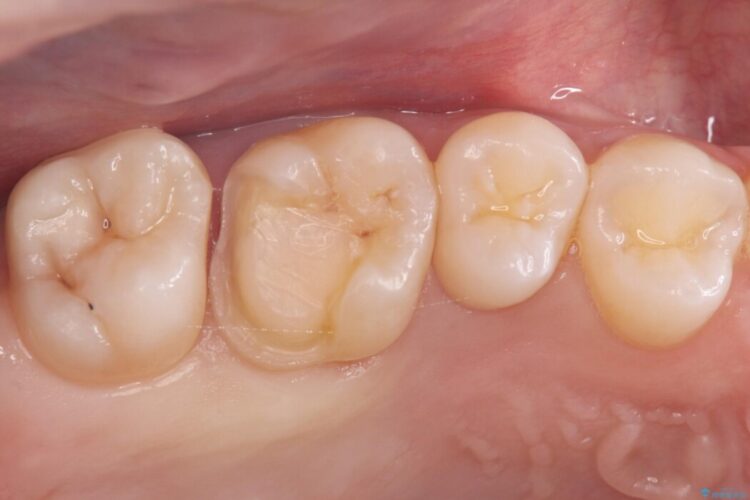

治療後について

セラミックアンレーセット時は、ラバーダム防湿を行っています。